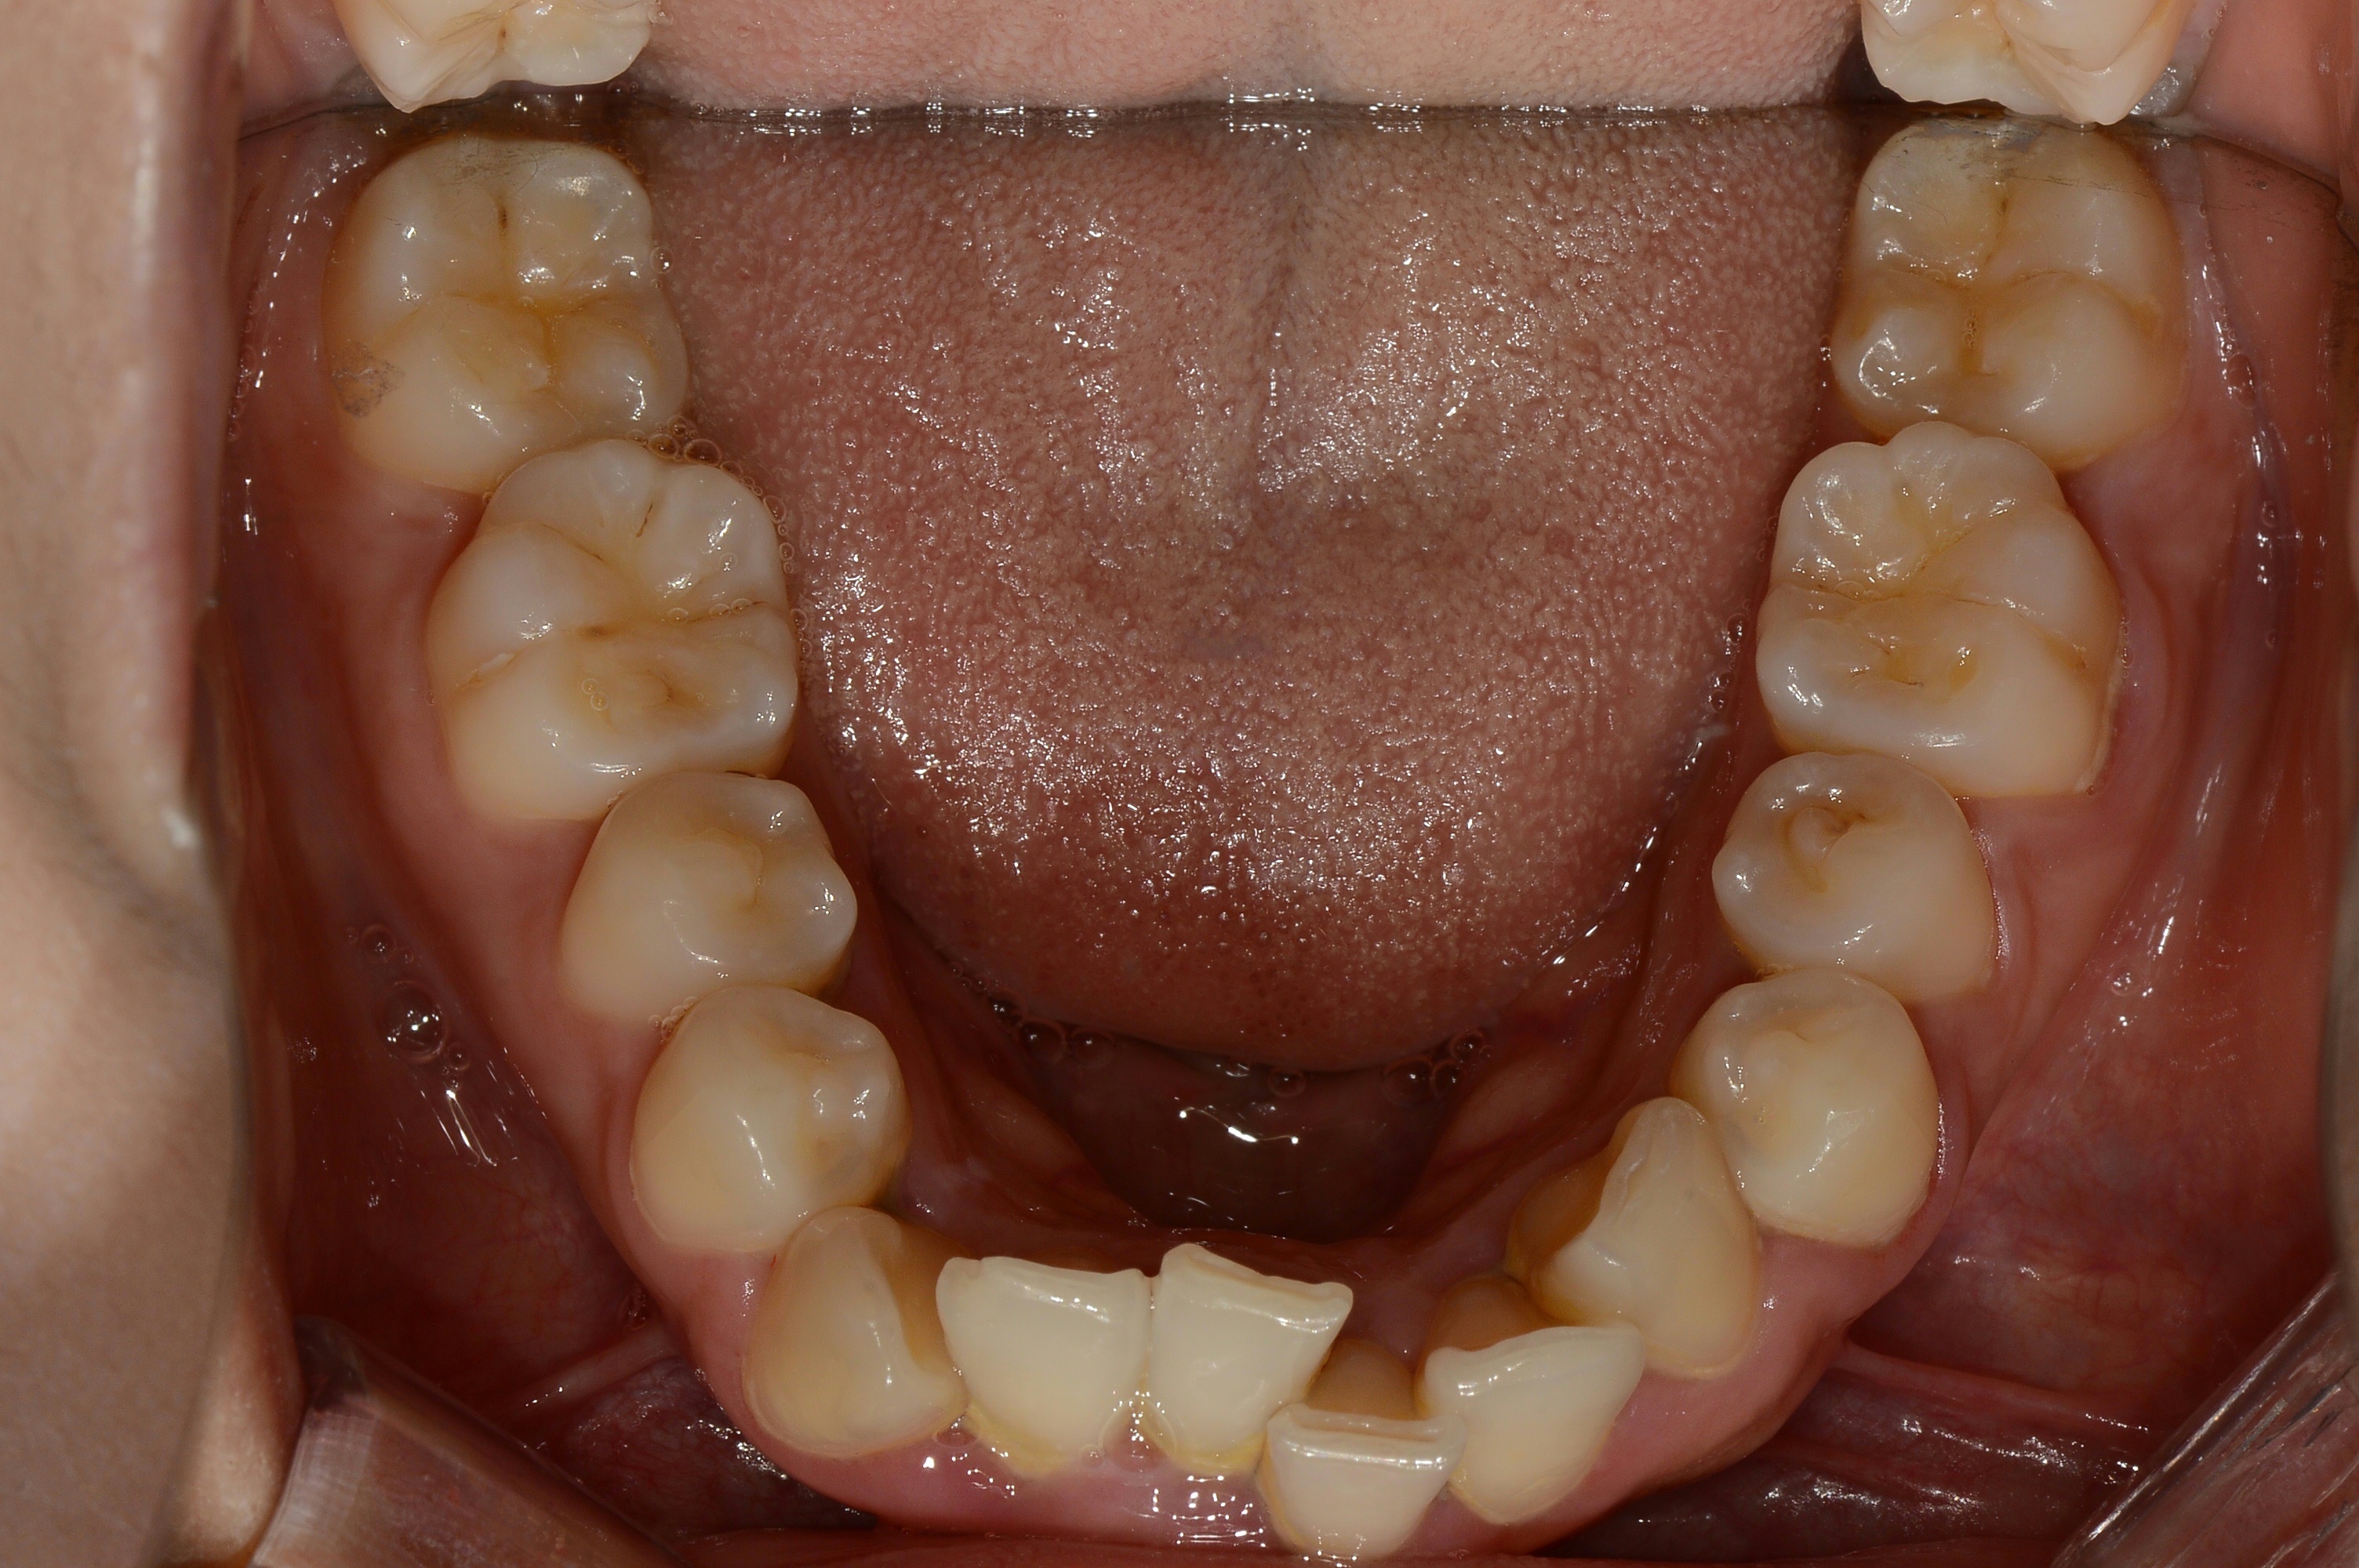

치료 후 사진입니다.